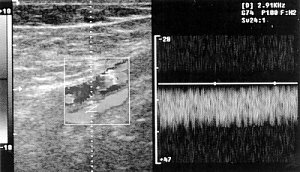

В норме контур стенок сосудов четкий, ровный, просвет эхонегативный. Ход магистральных артерий прямолинейный. Толщина комплекса интима-медиа не превышает 1 мм (по данным некоторых авторов - 1,1 мм). При допплерографии любых артерий в норме выявляется ламинарный кровоток (рис. 1).

Рис. 1. Продольное сканирование артерии. Магистральный тип кровотока.

Признак ламинарного кровотока - наличие "спектрального окна". Следует отметить, что при недостаточно точно скорригированном угле между лучом и потоком крови "спектральное окно" может отсутствовать и при ламинарном кровотоке. При допплерографии артерий шеи получается спектр, характерный для этих сосудов. При исследовании артерий конечностей выявляется магистральный тип кровотока. В норме стенки вен тонкие, стенка, прилежащая к артерии, может не визуализироваться. В просвете вен посторонних включений не определяется, в венах нижних конечностей визуализируются клапаны в виде тонких структур, колеблющихся в такт с дыханием. Кровоток в венах фазный, отмечается синхронизация его с фазами дыхательного цикла (рис. 2, 3).